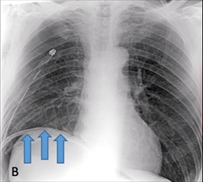

Figura 2. A: Drenaje pleural normoinserto, persistencia de espacio residual apical grande y enfisema subcutáneo

Figura 2 B: Radiografía post triple procedimiento, donde se observa elevación del hemidifragma izquierdo, disminución sustancial del espacio residual y neumoperitoneo terapéutico.